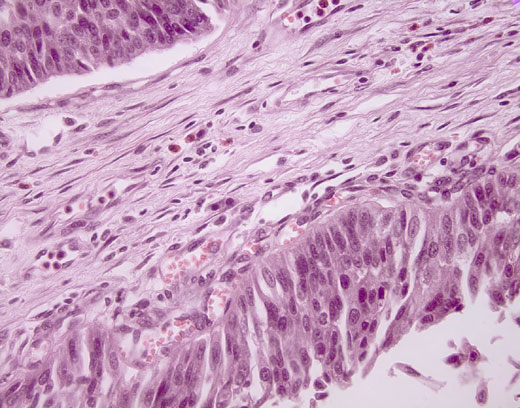

Cross-section #26 - 40X